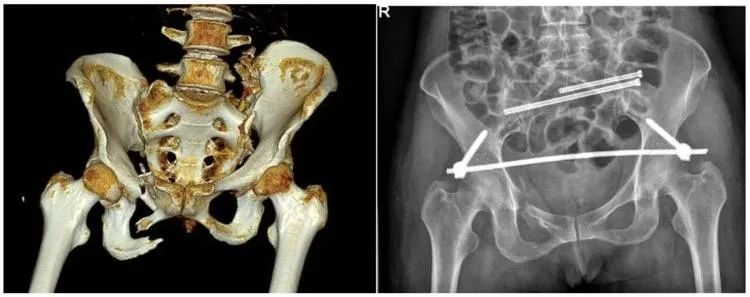

【醫(yī)療科普】:外傷性骨折影像

外傷性骨折

【醫(yī)療科普】:不穩(wěn)定性骨折影像

不穩(wěn)定性骨折